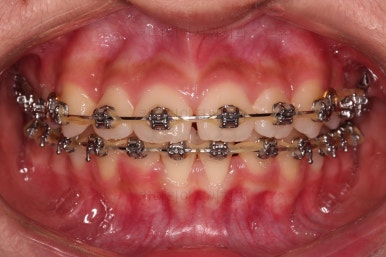

이번 환자분이 선택한 장치는 엠파워 메탈이라고 하는 자가결찰 금속 브라켓입니다.

메탈 브라켓이라고 다 구식의 안좋은 장치가 아닙니다.

"자가결찰" 브라켓이면 모두 우수한 성능의 장치인데요.

철사를 잡아주는(결찰) 캡이 브라켓에 달려 있어 스스로 묶을 수 있는(자가) 브라켓입니다.

즉, 세라믹 중에서도 자가결찰인 것이 있고 아닌 것이 있으며, 메탈 중에서도 자가결찰인 것이 있고 아닌 것이 있습니다.

장치를 부착한 직후의 얼굴 모습 변화와 장치가 보이는 느낌을 한 번 봐주시고요.

윗니가 가지런해진 뒤에는 부산치아교정치과 키다리아저씨치과에서는 ABP라고 하는 장치를 사용해 주면서 아랫니에도 브라켓을 부착합니다.

깊게 물리는 과개교합을 개선하기 위함인데요.

과개교합을 개선하기 위해서는 미니스크류를 사용하기도 하고 ABP를 사용하기도 하며, 윗니 앞니를 코 방향으로 밀어넣기도 합니다.

얼굴모습과 교합을 생각해서 각 케이스마다 모두 다른 방법을 적용해야 하므로 일관된 공식이 있는 것이 아닙니다.

이번 환자분은 ABP의 사용이 가장 적합했던 케이스였습니다.

ABP를 사용하지 않고도 과개교합이 매우 좋아졌고요.

위아래 치열이 매우 고르게 되었으며, 이제부터는 발치공간을 줄여나가면서 교합을 맞춰 나가면 됩니다.